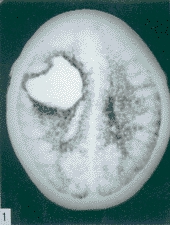

1.确定有无蛛网膜下腔出血。出血急性期,CT确诊SAH阳性串极高,安全迅速可靠。出血一周后,CT叮不易诊断。腰椎穿刺可能诱发动脉瘤破裂出血,故一般不再作为确诊SAH的首选。

2.因颅内动脉瘤多位于颅底部WiLLis动脉环,直径小于1.0C的动脉瘤,CT不易查出。直径大于1.0cm,注射对比剂后,CT扫描可检出。MRI忧于CT,动脉瘤内可见流空。MRA可提示不同部位动脉瘤,常用于颅内动脉瘤筛选。三维CT(3D-CT)从不同角度了解动脉瘤与载瘤动脉的关系,为手术夹闭动脉瘤决策提供更多的资料。